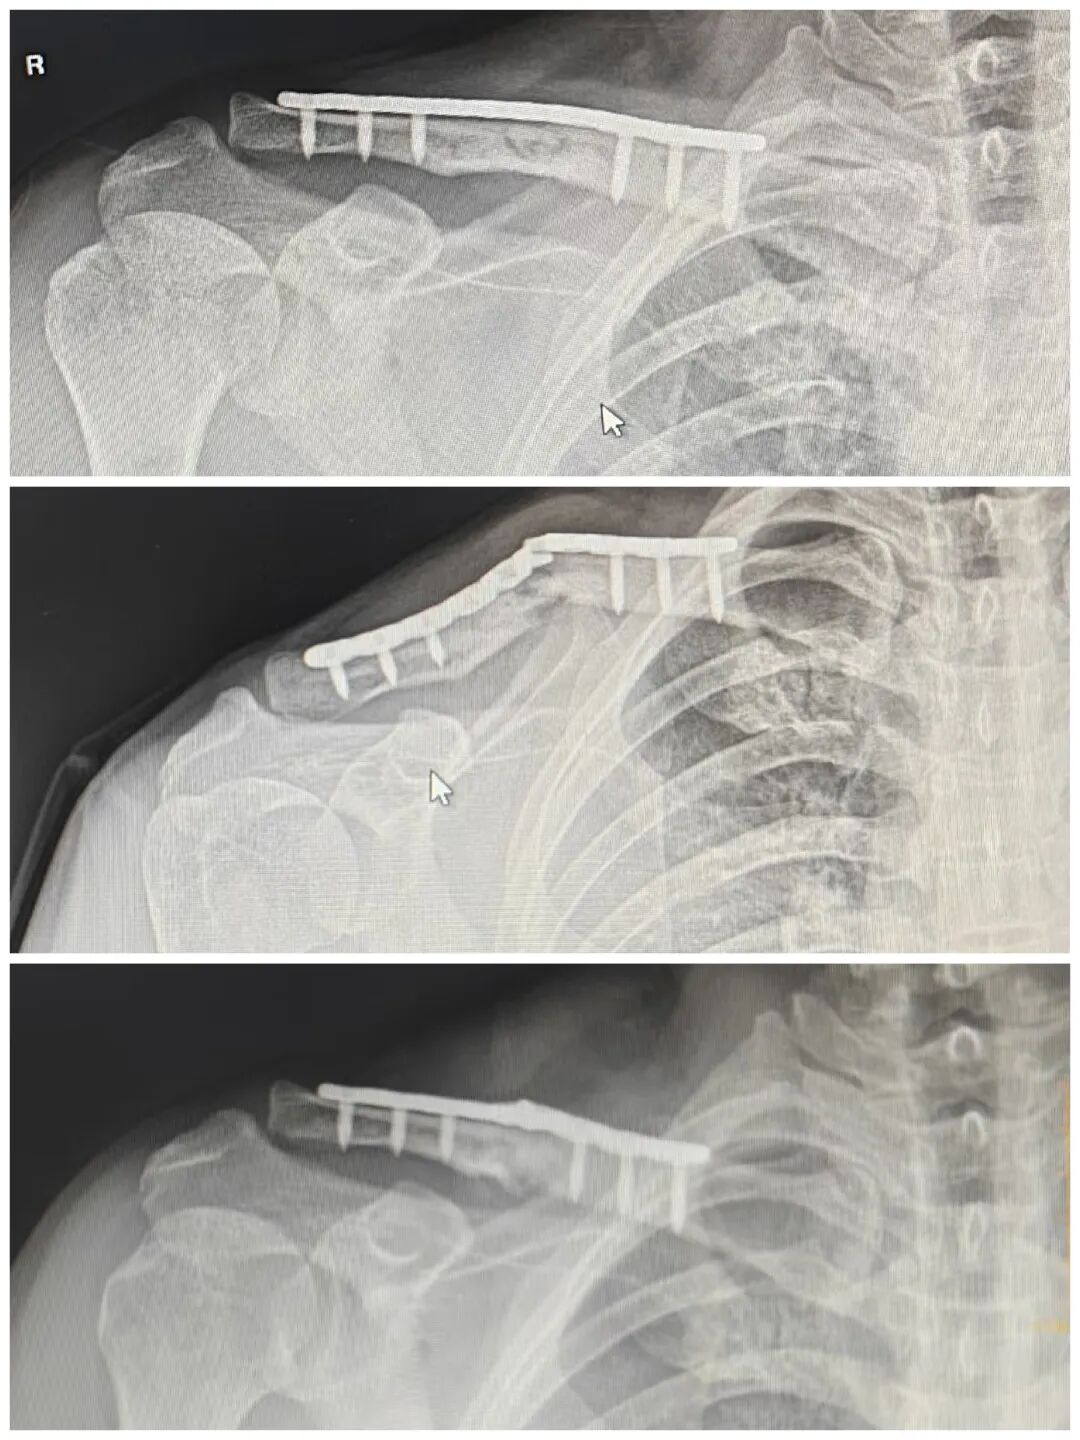

2个月后来复查

长势喜人

骨折愈合良好

断板也复位了